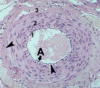

Identify the entire structure.

Identify the structure indicated by the arrowheads.

- elastic artery

- arrowheads: vaso vasorum

Elastic fibers in elastic arteries are synthesized by:

the smooth muscle cells.

Key feature of elastic arteries:

- sheets of elastin between layers smooth muscle cells